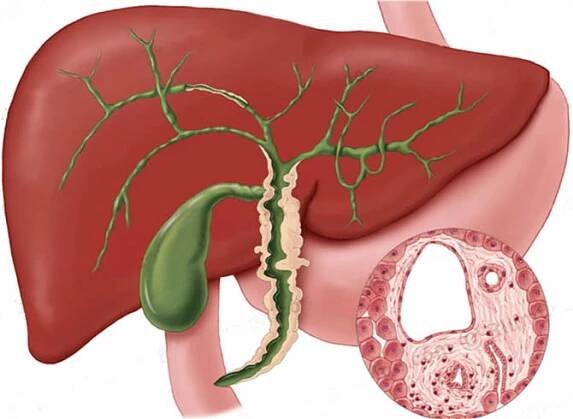

Cholestáza je definována jako porucha tvorby žluči v játrech nebo jejího toku, která může nastat kdekoliv mezi sinusoidální membránou hepatocytu a Vaterskou papilou.

Cholestáza znamená poruchu odtoku žluči a příznaky s tímto stavem spojené. Cholestáza může vzniknout na podkladě patologie nacházející se v játrech (intrahepatální cholestáza) i mimo jaterní tkáň (extrahepatální cholestáza).